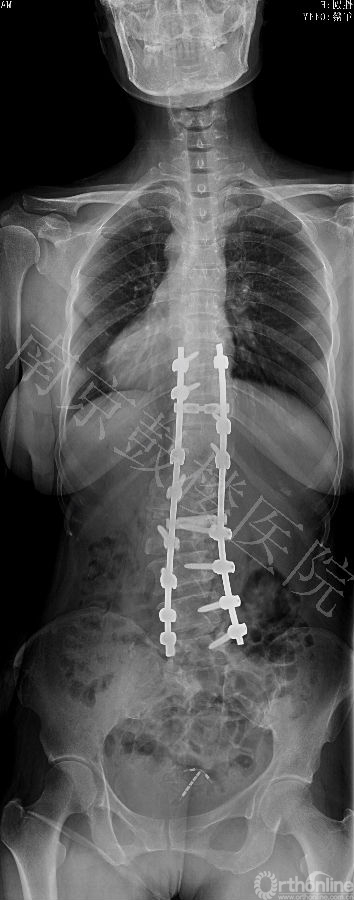

近日,南京鼓楼医院成功运用后路全脊椎截骨术和CDH Solera内固定矫形技术治疗一例先天性脊柱侧后凸成年患者。此为Solera内固定系统在中国的首例手术。

Solera系统是最新一代的CD Horizon产品,新增了独特的钴铬钉头设计和双螺纹设计,提高了钉头强度和螺钉把持力,固定棒有多种直径和材质供选择。该系统近年在欧美国家逐渐推广应用。

本例女,44岁,因严重的脊柱侧后凸畸形造成躯干塌陷,接受全脊椎截骨术和Solera内固定系统矫形手术,矫正率高达82%,无并发症发生。患者对手术效果非常满意。